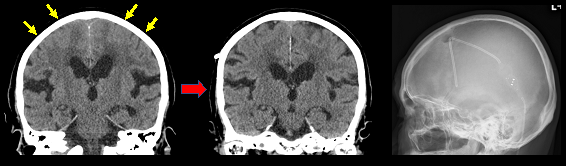

まず髄液排出試験(タップテスト)を約1週間の入院で施行し、神経心理検査(認知機能検査)および歩行機能を3日目まで詳細に評価します。適応のある方について髄液シャント術を提案します。脳室腹腔シャント術、脳室腰部くも膜下腔シャント術どちらも対応しますが、腰部の方を第一選択で考えます。術後も長期間フォローアップの方針で認知機能と歩行機能を定期的評価し、シャント圧設定を綿密に調節致します。画像上の改善とともに症状改善がみられる方が多いです。

図:正常圧水頭症に対する髄液シャント術(脳室シャント)、CTにて高位円蓋部の脳溝狭小や脳梁角の改善がみられる。